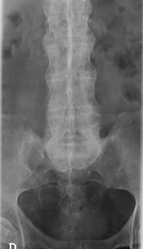

Fig 56 B. Espondilitis anquilosante.

A y B: Rx AP. La parte anterior de los cuerpos vertebrales es “cuadrada”, cambios que sugieren espondilitis anquilosante inicial.